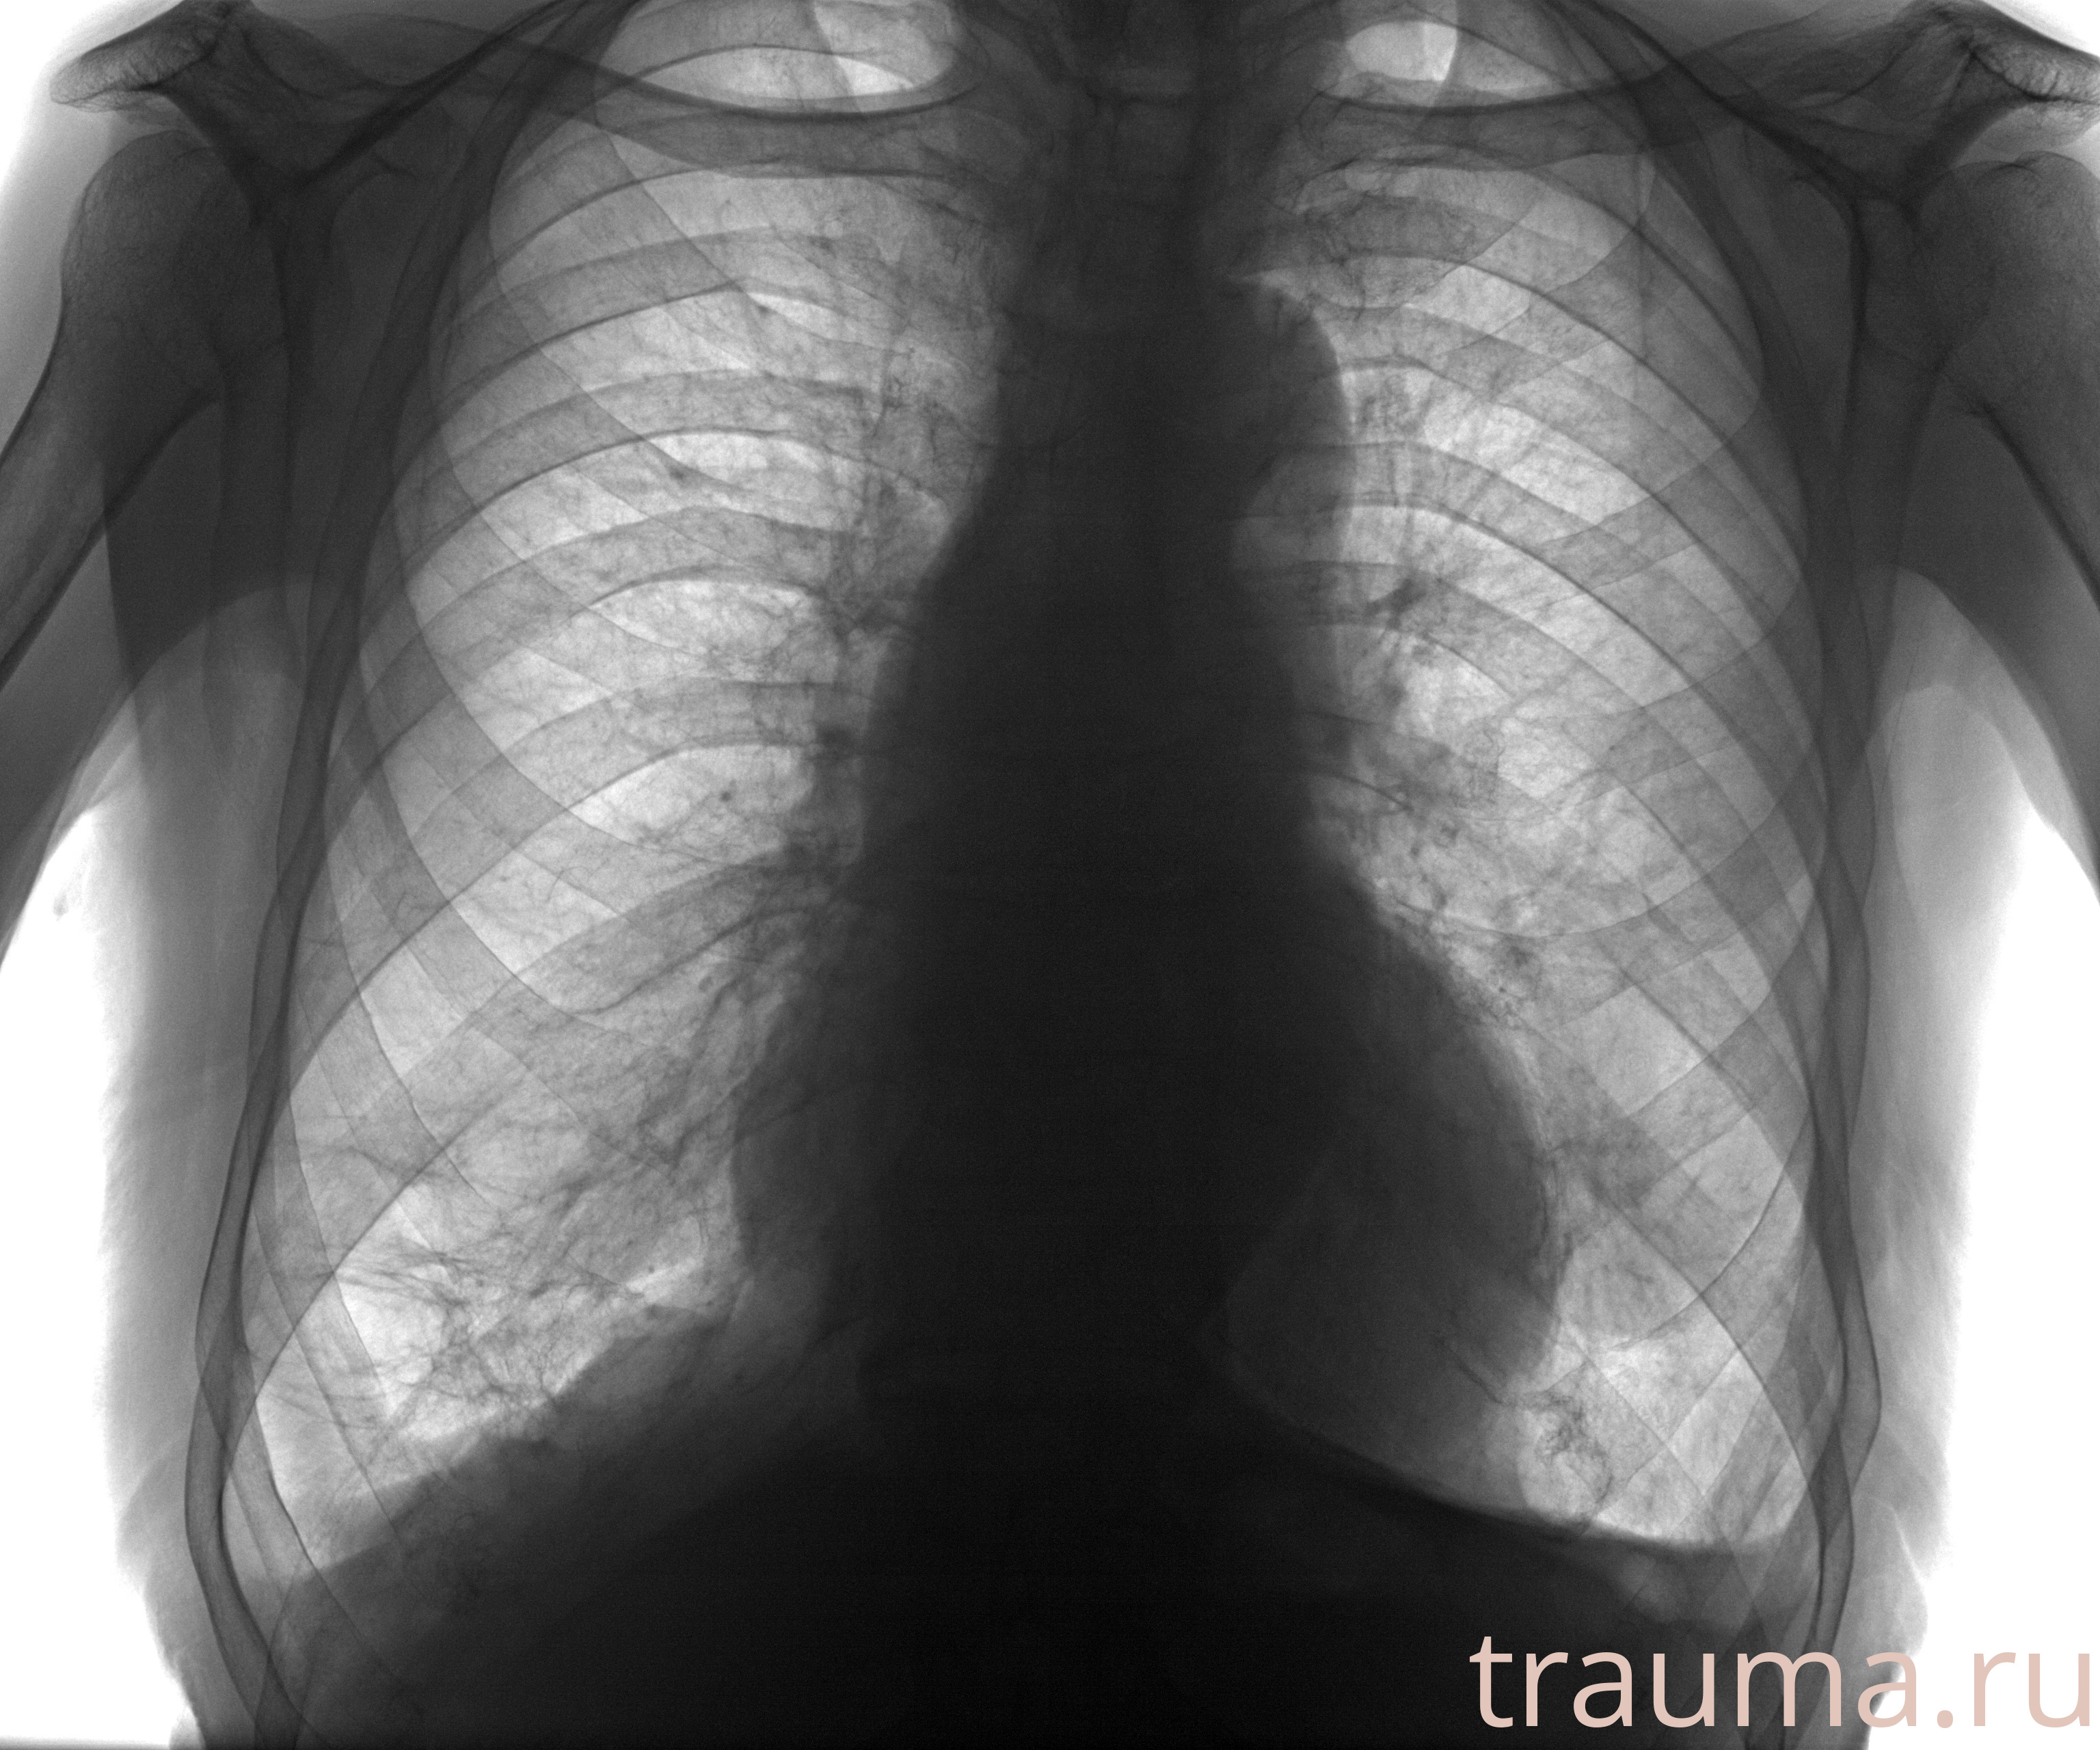

Рентген на дому: по вашему адресу приезжает врач-рентгенолог, травматолог-ортопед с мобильным рентгеновским аппаратом, проводит диагностику травмы или заболевания, делает необходимые рентгенограммы, дает рекомендации по дальнейшему лечению. Получить качественные снимки в домашних условиях возможно благодаря уникальной методике, разработанной МосРентген Центром для института  Склифосовского

при переломе шейки бедра и пневмонии от компании МосРентген Центр - партнера Института имени Склифосовского